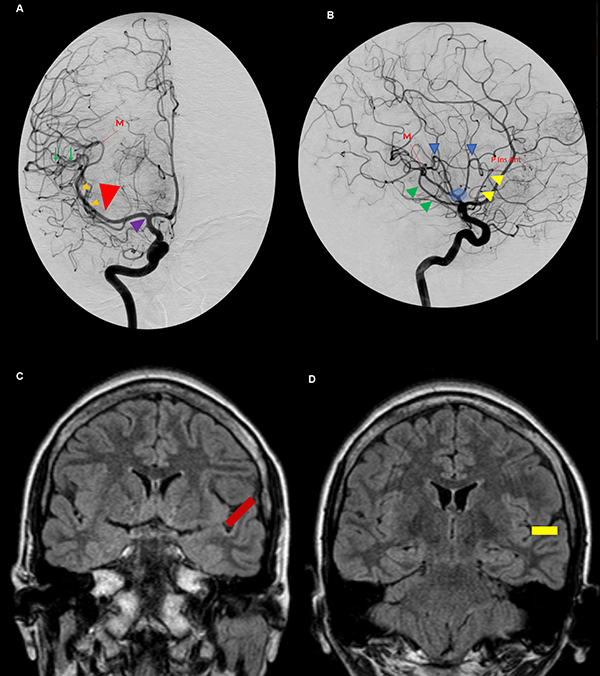

Figura 11: A. Vista anteroposterior de una angiografía carotídea derecha. El uncus (cabeza de flecha violeta) se relaciona anteriormente con el segmento proximal de M1. El ápex uncal apunta hacia la bifurcación carotídea. Inmediatamente distal al genu de la ACM se ubica la pars triangularis (cabeza de flecha roja grande). Las pequeñas cabezas de flecha naranjas indican el segmento M2 de la ACM y, consecuentemente, la corteza insular. El punto M se define como el punto donde el ramo más posterior de M2 cambia de sentido alejándose de la ínsula hacia el opérculo, en relación estrecha con el extremo posteromedial del giro de Heschl. La ínsula se proyecta desde el genu de la ACM hasta el punto M. Las ramas de M3 sobre el plano temporal tienen un curso recto (flechas verdes). B. Vista lateral de la misma angiografía. Se identifica el triángulo silviano. Su borde anterior (cabeza de flecha amarillo) y superior (cabezas de flecha azul) lo marcan los loops de M2. Su borde inferior lo indica el tronco inferior de M2 cursando por el surco limitante inferior insular (cabeza de flecha verde). Los troncos postbifurcación se ramifican cerca del polo insular y el ápex (círculo celeste). C y D. Vistas coronales de una RMN. El plano polar tiene una dirección oblicua inferior (barra roja) (C) y el plano temporal una dirección recta (barra amarilla) (D). P Ins Ant: punto insular anterior.

Se dice que la angiografía digital (AD) muestra el esqueleto en el cual las estructuras neurales son organizadas. Su comprensión profunda es esencial para el planeamiento quirúrgico. La corteza insular está cubierta e irrigada por el segmento M2 (Figura 7A). Consecuentemente, en una AD, el lóbulo insular se localiza inmediatamente medial a M2 (Figura 11A y B).21 Los límites anterior, superior e inferior del lóbulo insular también pueden ser reconocidos en la AD. Los puntos de cambio de dirección, o loops, de la ACM distal al genu marcan la transición M2/M3 y se localizan en el surco limitante insular anterior y superior (Figura 7A y B). El tronco inferior de M2 cursa a lo largo del surco limitante inferior (Figura 7A). El punto donde el ramo más posterior de M2 cambia de dirección y se aleja de la ínsula dirigiéndose hacia el opérculo temporal (transición M2/M3) es el punto M o silviano, en la AD (Figura 12B, 11A, 11B).12,14,15,26,30 El punto M es un reparo imagenológico de gran utilidad. Este punto indica el extremo posterior insular y la parte más posteromedial del giro de Heschl. Así también, en una incidencia anteroposterior, el punto M indica la posición de, de lateral a medial, el brazo posterior de la cápsula interna, el pulvinar del tálamo y el atrio (Figura 12B).

El triángulo silviano6,14,15 es un reparo encontrado en la incidencia lateral estricta en un AD. Sus bordes son dibujados por los loops M2 anterior y superiormente, y por el tronco inferior cursando por el surco limitante inferior insular, inferiormente. Este triángulo tiene un ángulo superoanterior recto, marcando el punto insular anterior. El contenido de este triángulo es el lóbulo insular y el core central. Inmediatamente por fuera del triángulo se encuentran los ventrículos laterales (Figura 11B).

La bifurcación carotídea se relaciona con el ápex uncal y el segmento proximal de M1 se relaciona inferiormente con el segmento anterior del uncus. Más aún, el genu de M1 se localiza en el limen insular, por lo tanto, en una AD, marca el borde anterior de la ínsula. La pars triangularis está ubicada unos milímetros distales al genu de M1. Dado que el giro precentral cubre el tercio medio de la ínsula, se puede inferir que el giro precentral en una AD se localiza en el punto medio del triángulo silviano. Finalmente, el extremo posterior del lóbulo insular se localiza en el punto M. Consecuentemente, lesiones vascularizadas localizadas en el genu de M1, son encontradas unos pocos milímetros proximales a la pars triangularis, cerca del polo insular; lesiones localizadas inmediatamente distal al genu, se relacionan superficialmente con la punta de la pars triangularis; y aquellas posicionadas en el punto medio entre el genu y el punto M, son mediales al giro precentral (Figura 11A y B).15

Las ramas M3 que cursan sobre el plano polar son más curvilíneas que aquellas del plano temporal, a causa de la superficie relativamente más plana de la primera. El primer segmento recto de M3 identifica el extremo lateral del giro de Heschl (Figura 11A).15 Entonces, el giro de Heschl está enmarcado entre el punto M y el primer tramo recto de M3 (Figura 7B).

El segmento M2 comienza en el punto en donde el segmento M1 cambia de dirección. Este punto se conoce como la rodilla o genu de la ACM y se localiza en el limen insular (Figura 9). El segmento M1 tiene una orientación mediolateral, perpendicular al punto de vista del neurocirujano; el segmento M2, una orientación inferosuperior, paralela al punto de vista del neurocirujano (Figura 10C). Durante la cirugía, una manera de diferenciar el segmento M1 de M2 es observando su dirección. El 80% de las bifurcaciones de la ACM se localizaron en o proximal al limen insular.